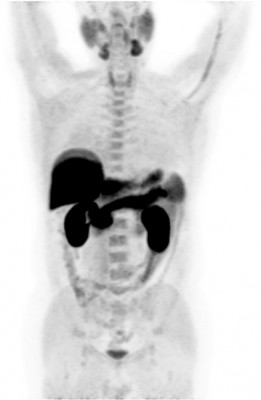

| Норма | Метастазы рака предстательной железы | Метастазы рака предстательной железы |